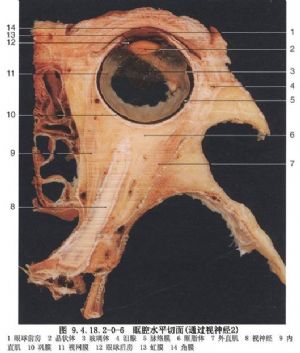

(1)视神经管:位于蝶骨,管内通过视神经、眼动脉和交感神经纤维。由于视神经管鼻侧壁就是蝶窦的窦壁,当蝶窦炎时,炎症可直接构成对视神经的威胁,引起视神经炎(图9.4.18.2-0-5,9.4.18.2-0-6)。

视神经孔为神经管在眼眶的开口,位于蝶骨小翼和蝶骨体之间,从颅脑通向眼眶,长6~8mm,此管由蝶骨小翼根将其与眶上裂隔开,视神经、眼动脉和伴随的交感神经纤维由此管通过,视神经占大部分,眼动脉位于视神经的外下方。在正常情况下,成人视神经管的眶侧端直径不大于6.5mm,称为视神经孔。